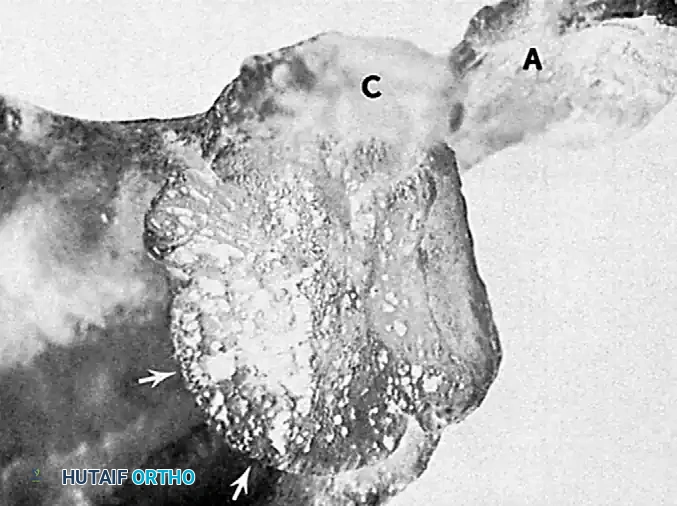

As illustrated above, in an old anterior dislocation, adhesions of the posterior capsule to the glenoid surface develop. Conversely, in an old posterior dislocation, adhesions of the anterior capsule to the glenoid surface develop.

In chronic anterior dislocations, a massive compression fracture occurs in the posterolateral aspect of the humeral head where it continuously impinges against the hard anterior glenoid rim. Because of the repeated, forceful efforts of the patient to achieve normal motion in the locked joint, this lesion is often substantially larger than the classic Hill-Sachs lesion seen in recurrent, episodic anterior dislocations.

Furthermore, the constant friction and pressure lead to compression fractures and severe wear of the apposing anterior glenoid rim. In long-standing cases, the body attempts to adapt by forming a pseudoarticulation (false joint) between the displaced humeral head and the anterior aspect of the scapula.

Posterior Dislocations:

In chronic posterior dislocations, a similar but reversed bony lesion is found. This is a compression fracture caused by the impingement of the posterior rim of the glenoid on the anteromedial aspect of the humeral head (often termed a "reverse Hill-Sachs" or McLaughlin lesion). Like their anterior counterparts, these lesions are usually massive due to the patient’s continual attempts to increase the range of motion against a fixed bony block.